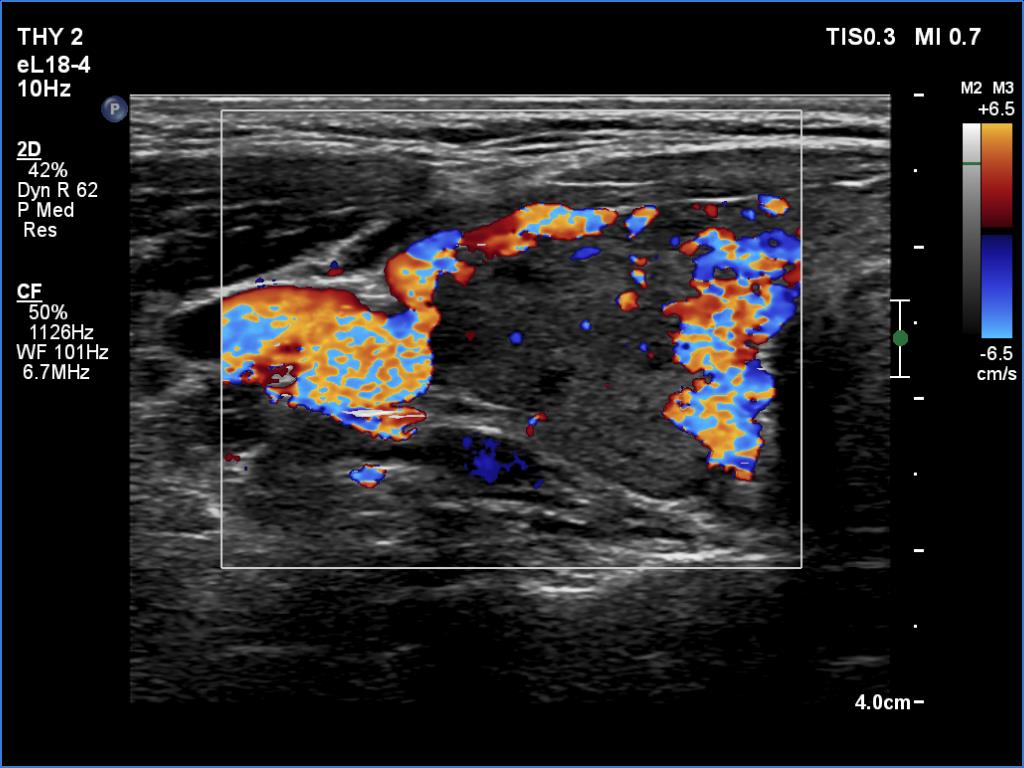

Right lobe, microflow imaging

Summary of ultrasound and laboratory data:

First examination - additional clinical data: A 27-year-old woman was referred for evaluation. She gave birth seven months ago. In the following months, she experienced significant weight loss, sweating, and a high heart rate. Symptoms significantly diminished by the time of the first study.

Second examination - additional clinical data: The patient's previous symptoms recurred two weeks before the study.

This is the typical course of a Graves' hyperthyroidism which does not relapse within a year. As the hormone result improves, both the size of the initially enlarged goiter and the degree of hypoechogenicity decrease.